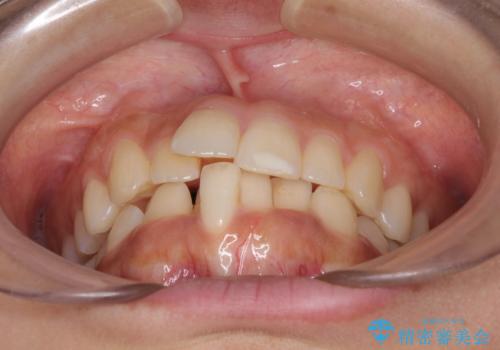

- 飛び出した前歯と全体的なデコボコを気にして来院された患者様です。

ワイヤーでもマウスピースでも治療可能でしたが、自己管理の重要なマウスピース矯正は自分には向かないとのことで、ワイヤー矯正で治療することとしました。

上下歯列全体を後方に移動させるため、親知らずは全て抜歯することにしました。